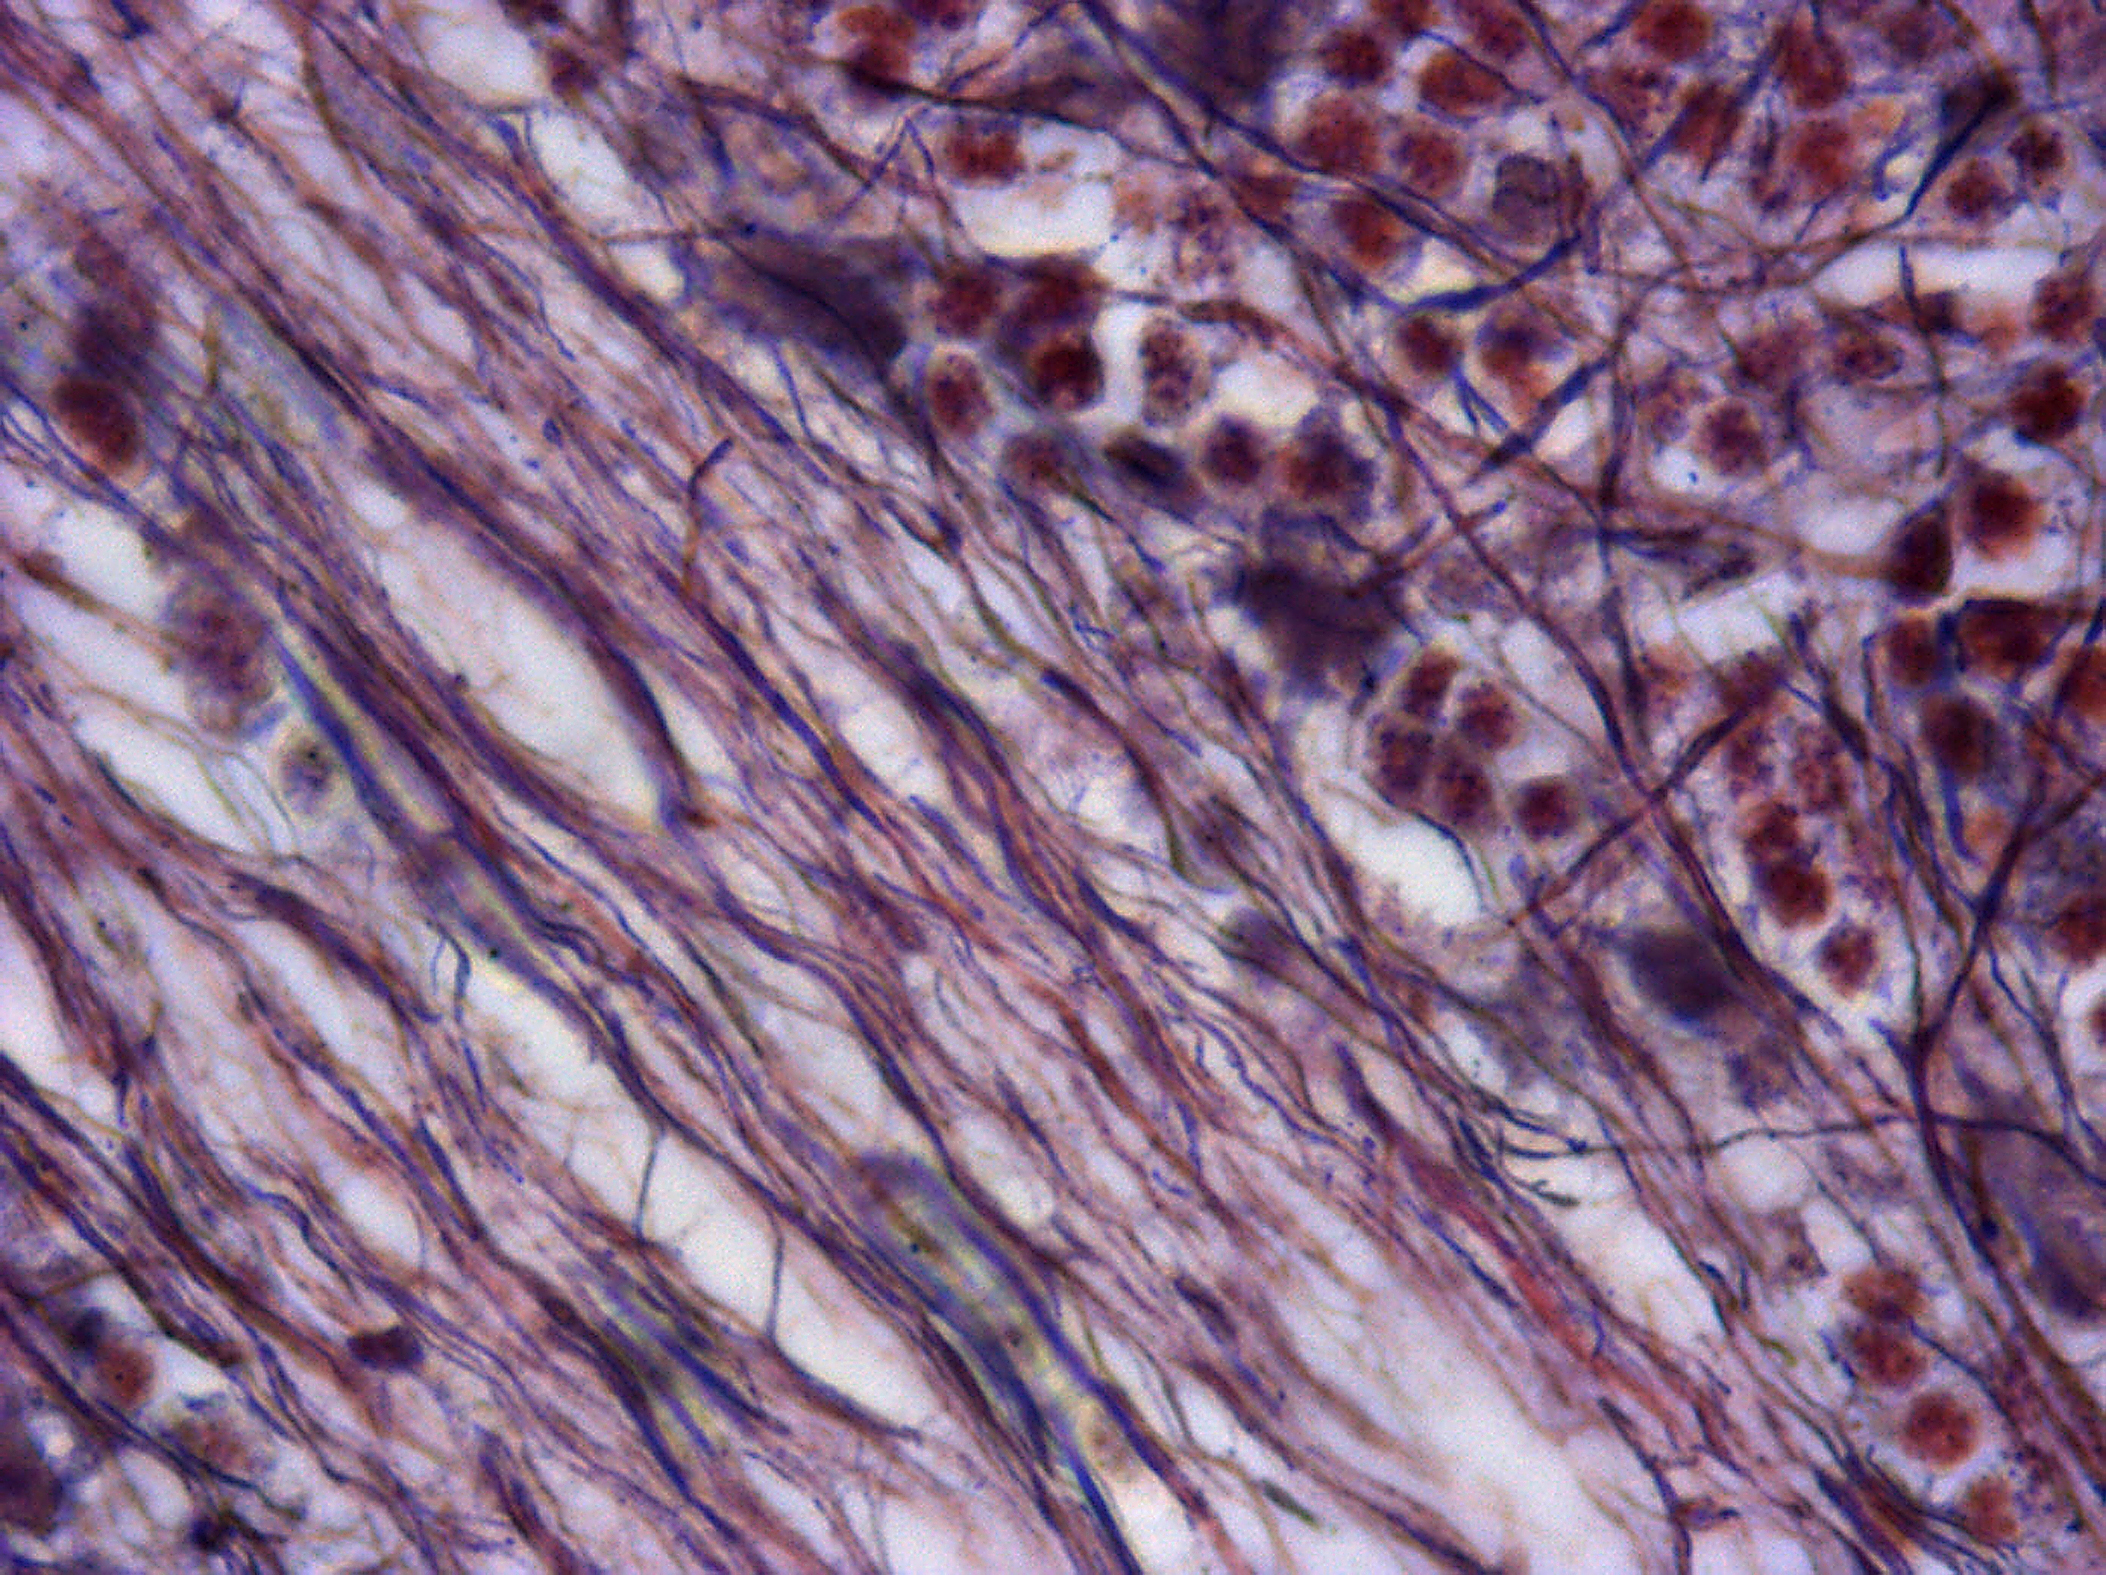

Axones du cervelet de souris (X100)

Coloration de Holmes